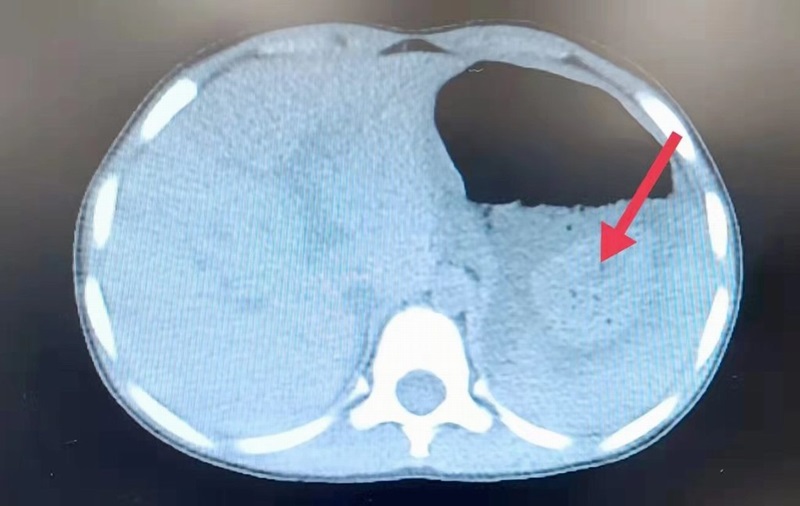

วันที่ 23 กุมภาพันธ์ 2565 เว็บไซต์เซาธ์ไชน่ามอร์นิ่งโพสต์ เผยว่า เด็กหญิงอายุ 4 ขวบ รายหนึ่ง ในเมืองเซี่ยงไฮ้ ประเทศจีน เข้ารับการรักษาในโรงพยาบาล เมื่อวันที่ 15 กุมภาพันธ์ ภายหลังจากมีอาการปวดท้องรุนแรง และอาเจียนเป็นเลือด ก่อนแพทย์ตรวจสอบพบว่า มีนิ่วขนาดใหญ่อยู่ในท้องของเธอ

ศาสตราจารย์หวง อิง ผู้อำนวยการแผนกระบบทางเดินอาหารของโรงพยาบาล เผยว่า จากตรวจเช็กร่างกายและประวัติทางการแพทย์ รวมทั้งพูดคุยกับผู้ปกครองของเด็กหญิงเกี่ยวกับการรับประทานอาหารเมื่อเร็ว ๆ นี้ สรุปว่า สิ่งแปลกปลอมในท้องของเธอ เป็นนิ่วในกระเพาะอาหารขนาดใหญ่ ซึ่งเกิดจากการกินลูกพลับมากเกินไป

โดยรายงานระบุว่า เด็กหญิงกินลูกพลับแห้งขณะท้องว่างจำนวน 6 ลูก จึงส่งผลให้เกิดการอุดตันของนิ่วในกระเพาะอาหาร และมีเลือดออกในกระเพาะ อีกทั้งยังมีแผลที่มีเส้นผ่านศูนย์กลางประมาณ 1 เซนติเมตร

ศาสตราจารย์หวง กล่าวว่า ในลูกพลับมีสารที่เรียกว่า กรดแทนนิก เมื่อสัมผัสกับกรดในกระเพาะ จะเปลี่ยนจากโปรตีนในผลไม้กลายเป็นก้อนหิน กระจุกตัว และจะแข็งขึ้นเมื่ออยู่ในกระเพาะนานขึ้น ในกรณีของเด็กหญิงรายนี้ นิ่วของเธอมีความยาวมากกว่า 4 เซนติเมตร